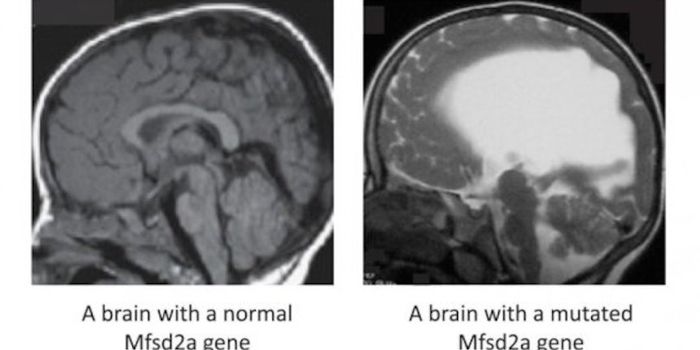

AUG 05, 2019Health & MedicineThe human brain is the most complex and least-understood part of the our body. With 86 billion brain cells and as many a ...